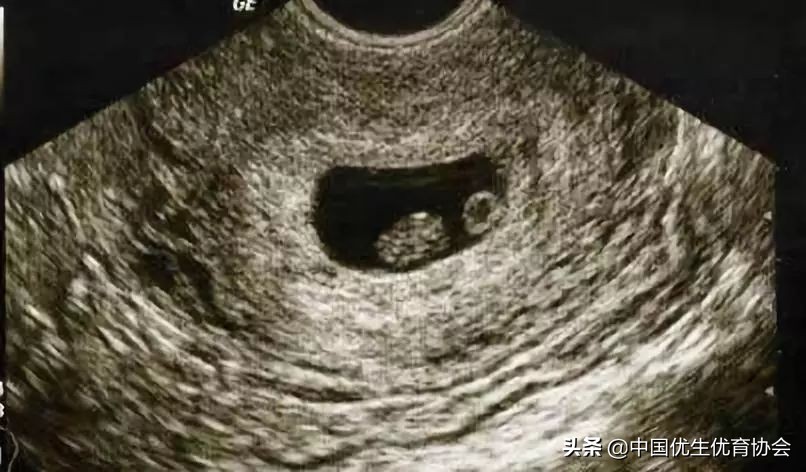

超声检查

超声检查是为了确定宫内孕,排除异位妊娠和其他跟怀孕有关的疾病。但是宝宝从受精到着床,到超声探头下可以探及是需要时间的,一般停经35天,宫腔内可以看到一个圆形的妊娠囊,停经6周可以看见胚芽和原始心管搏动。

月经不规律的宝妈注意啦,若HCG阳性,但超声没有探及妊娠囊,莫急,除了警惕宫外孕的同时,也可能是受精时间晚,胎囊还没有长出来。而早孕期的超声可以帮助末次月经记不清及月经不规律的妈妈确认孕周,推算预产期及之后的孕期检查。